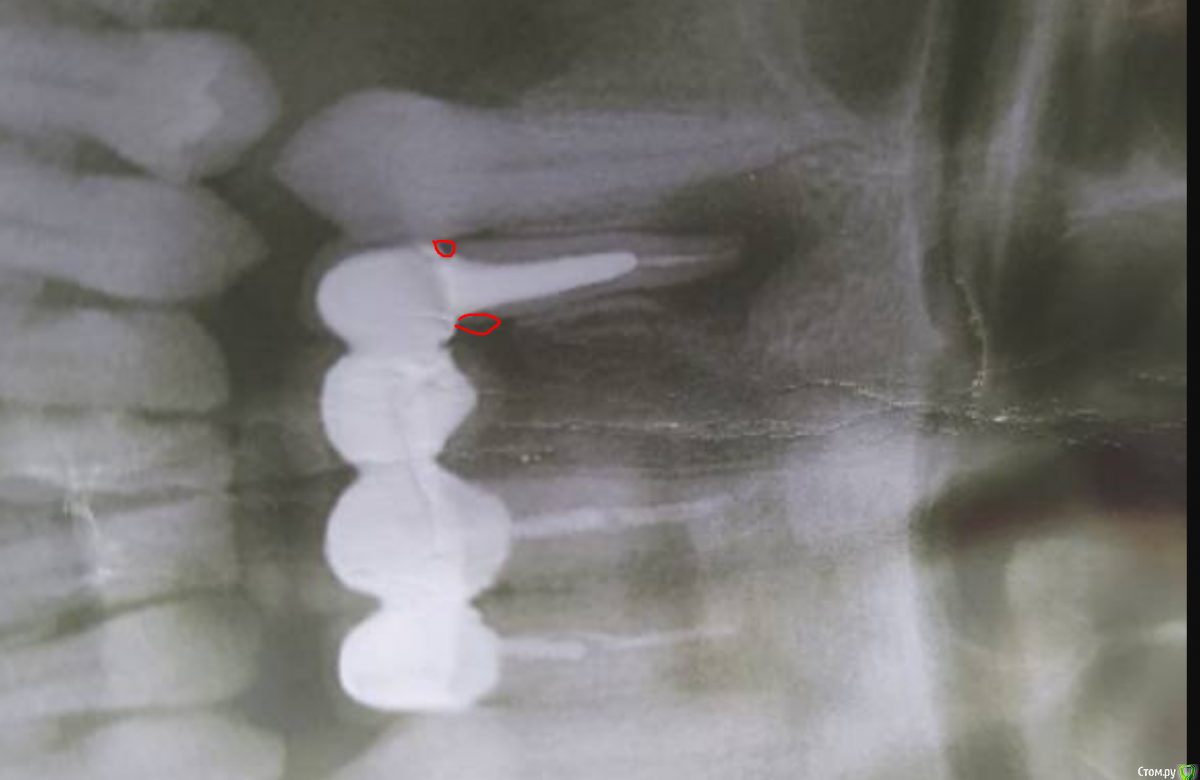

Olga1610 Опубликовано 14 апреля, 2020 Поделиться Опубликовано 14 апреля, 2020 Добрый день. Менее года назад поставила мост на 4 передних зуба, около 2 недель назад над крайним зубом появился шарик с гноем, он лопается через несколько дней и появляется заново... На снимке над этим зубом большая гранулёма.. подскажите, возможна ли в данной ситуации резекция верхушки корня? Снимать мост, удалять зуб и ставить новый мост я сейчас финансово никак не потяну(( https://c.radikal.ru/c17/2004/aa/637a20902980.jpg Ссылка на комментарий

It'sGeorgy Опубликовано 14 апреля, 2020 Поделиться Опубликовано 14 апреля, 2020 Не по теме немного. Красным отмечены "зазоры" между коронкой и корнем зуба. Туда на постоянной основе попадает пища, что способствует появлению кариеса на корне зуба. Вам крайне желательно купить ирригатор и начать им пользоваться, чтобы хоть как-то начать вычищать эти промежутки. Ссылка на комментарий

Zlata-doctor Опубликовано 14 апреля, 2020 Поделиться Опубликовано 14 апреля, 2020 Очень большой дефект. Прогноз по данному зубу неблагоприятный. Вкладка огромная, нет ли там перелома? Это весьма вероятно, но на снимке не увидеть. Как "последний шанс" можно сделать резекцию, но да, ищите грамотного оператора, работающего с увеличением, кто может ретроградно запломбировать. ( А также кто прокрасит корень и посмотрит, нет ли там трещины). Можно пока ничего не делать, учитывая ситуацию с Covid, у вас формируется свищ, через который идет отток продуктов воспаления. 2 Ссылка на комментарий